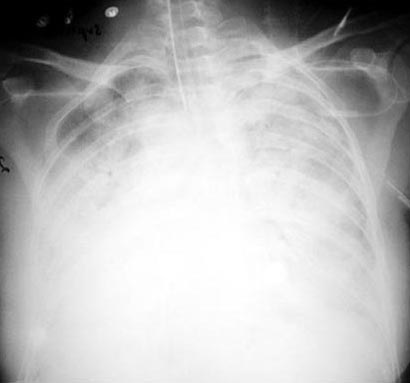

ARDS

• Diffuse white out of lung fields

• Diffuse alveolar atelectasis